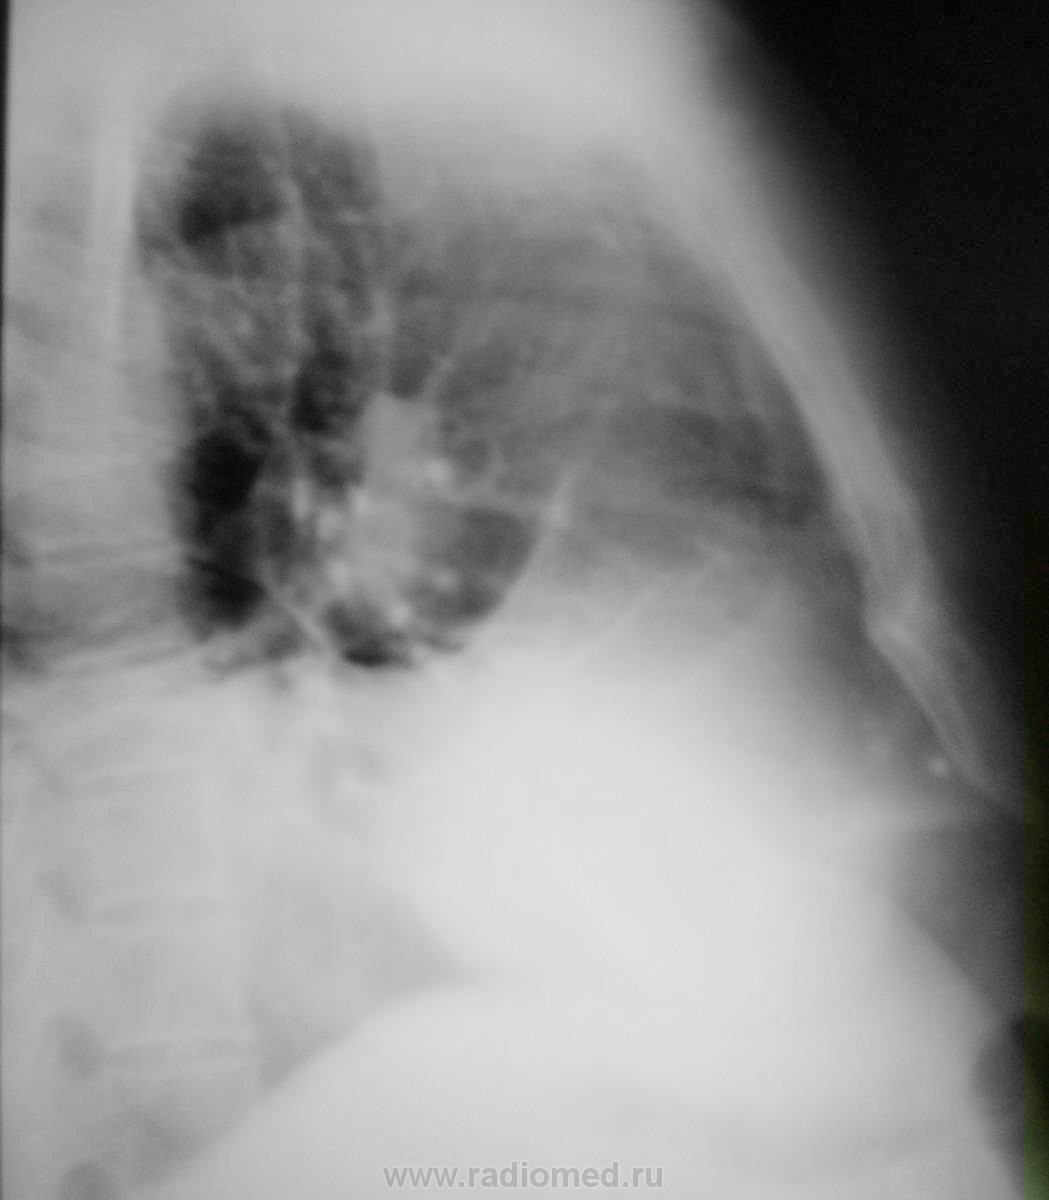

Массивное затемнение "вне анатомических границ", чаще всего дает выпот.

Снимки.

И слева, кажется, тоже.Выпот, даже не сомневайтесь.Причем "добрый"( в смысле, жидкости много).

Правосторонний средний гидроторакс. Позвонки одинаковой высоты.

Коллеги! А на ателектаз нижней и средней долей совсем не похоже?

Потянул-бы, если-бы выпота справа не было. А так плюс - на минус - средостение-то на месте, при значительном выпоте справа.

Стоит подумать над версией предложенной коллегой lupan